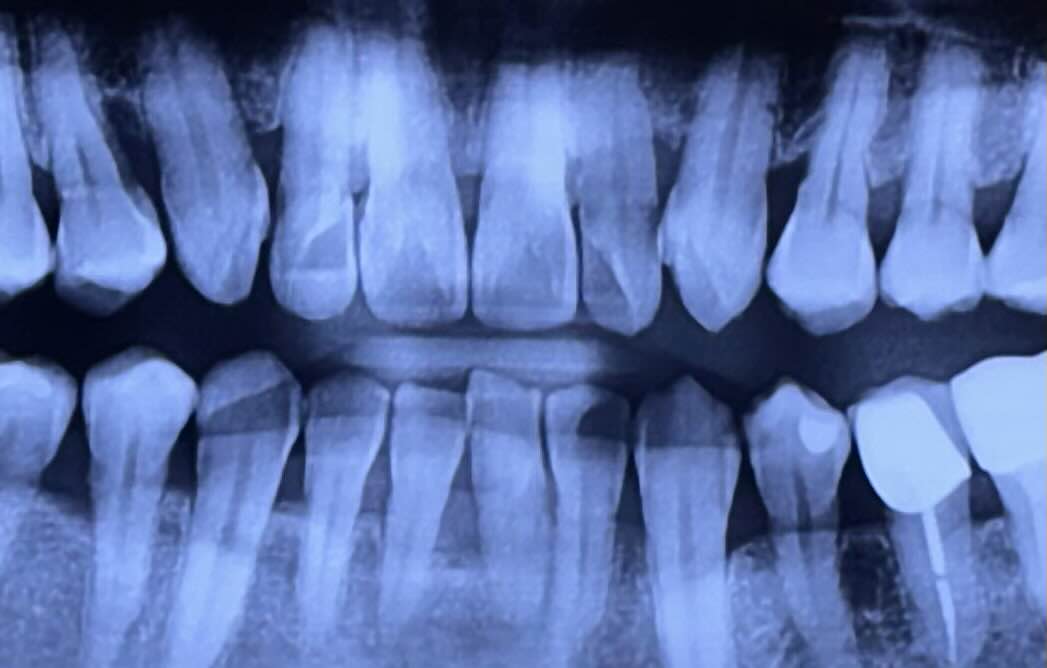

최근에 간헐적인 흡연도 완전히 끊은 후에 스케일링을 위해 치과를 찾았다. 의사선생님이 오른쪽 위쪽 어금니를 가리키며 아프지 않으세요?라고 물었다.

잇몸이 많이 녹아내려 어금니 "임플란트"가 필요할 것 같다고 했다.

의사선생님은 별거 아니단 듯이 임플란트 과정을 내 치아 엑스레이를 보며 친절하게 설명해 주었다.

어금니 안쪽에 있는 사랑니도 발치해야 한다. 준비과정을 거쳐 발치 후 임플란트를 심기까지 5-6개월이 걸릴 수 있다고 했다.